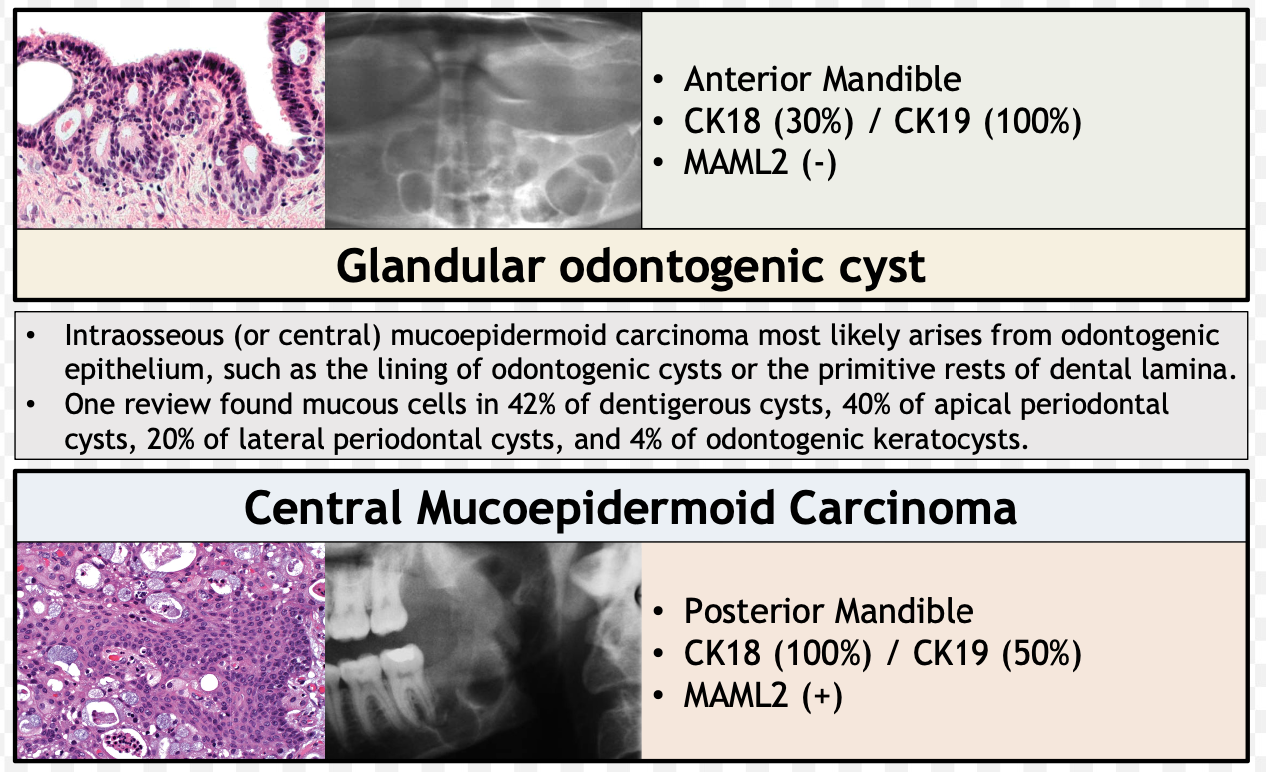

| Glandular Odontogenic Cyst (GOC) | - | 下顎前牙 | 46-51y | 跨中線、無 MAML2 | |

復發、局部侵犯性,吃 cortical bone  |

|||||

| 杯狀細胞, cilia, focal plaques | |||||

MAL2 讓 MEC 預後好